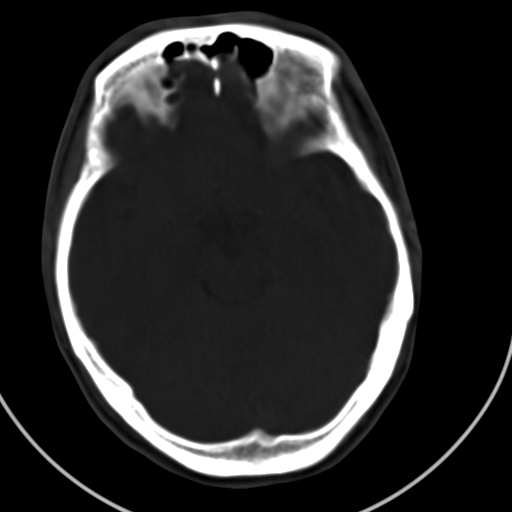

标题: CT21939:男20岁,外伤一年后,现头疼. [打印本页]

标题: CT21939:男20岁,外伤一年后,现头疼.

颅骨凹陷性骨折并压迫脑组织致大脑镰下疝!

硬膜外血肿伴包膜钙化

左侧额部硬膜外血肿机化、骨化。

左侧额部硬膜外血肿机化、骨化